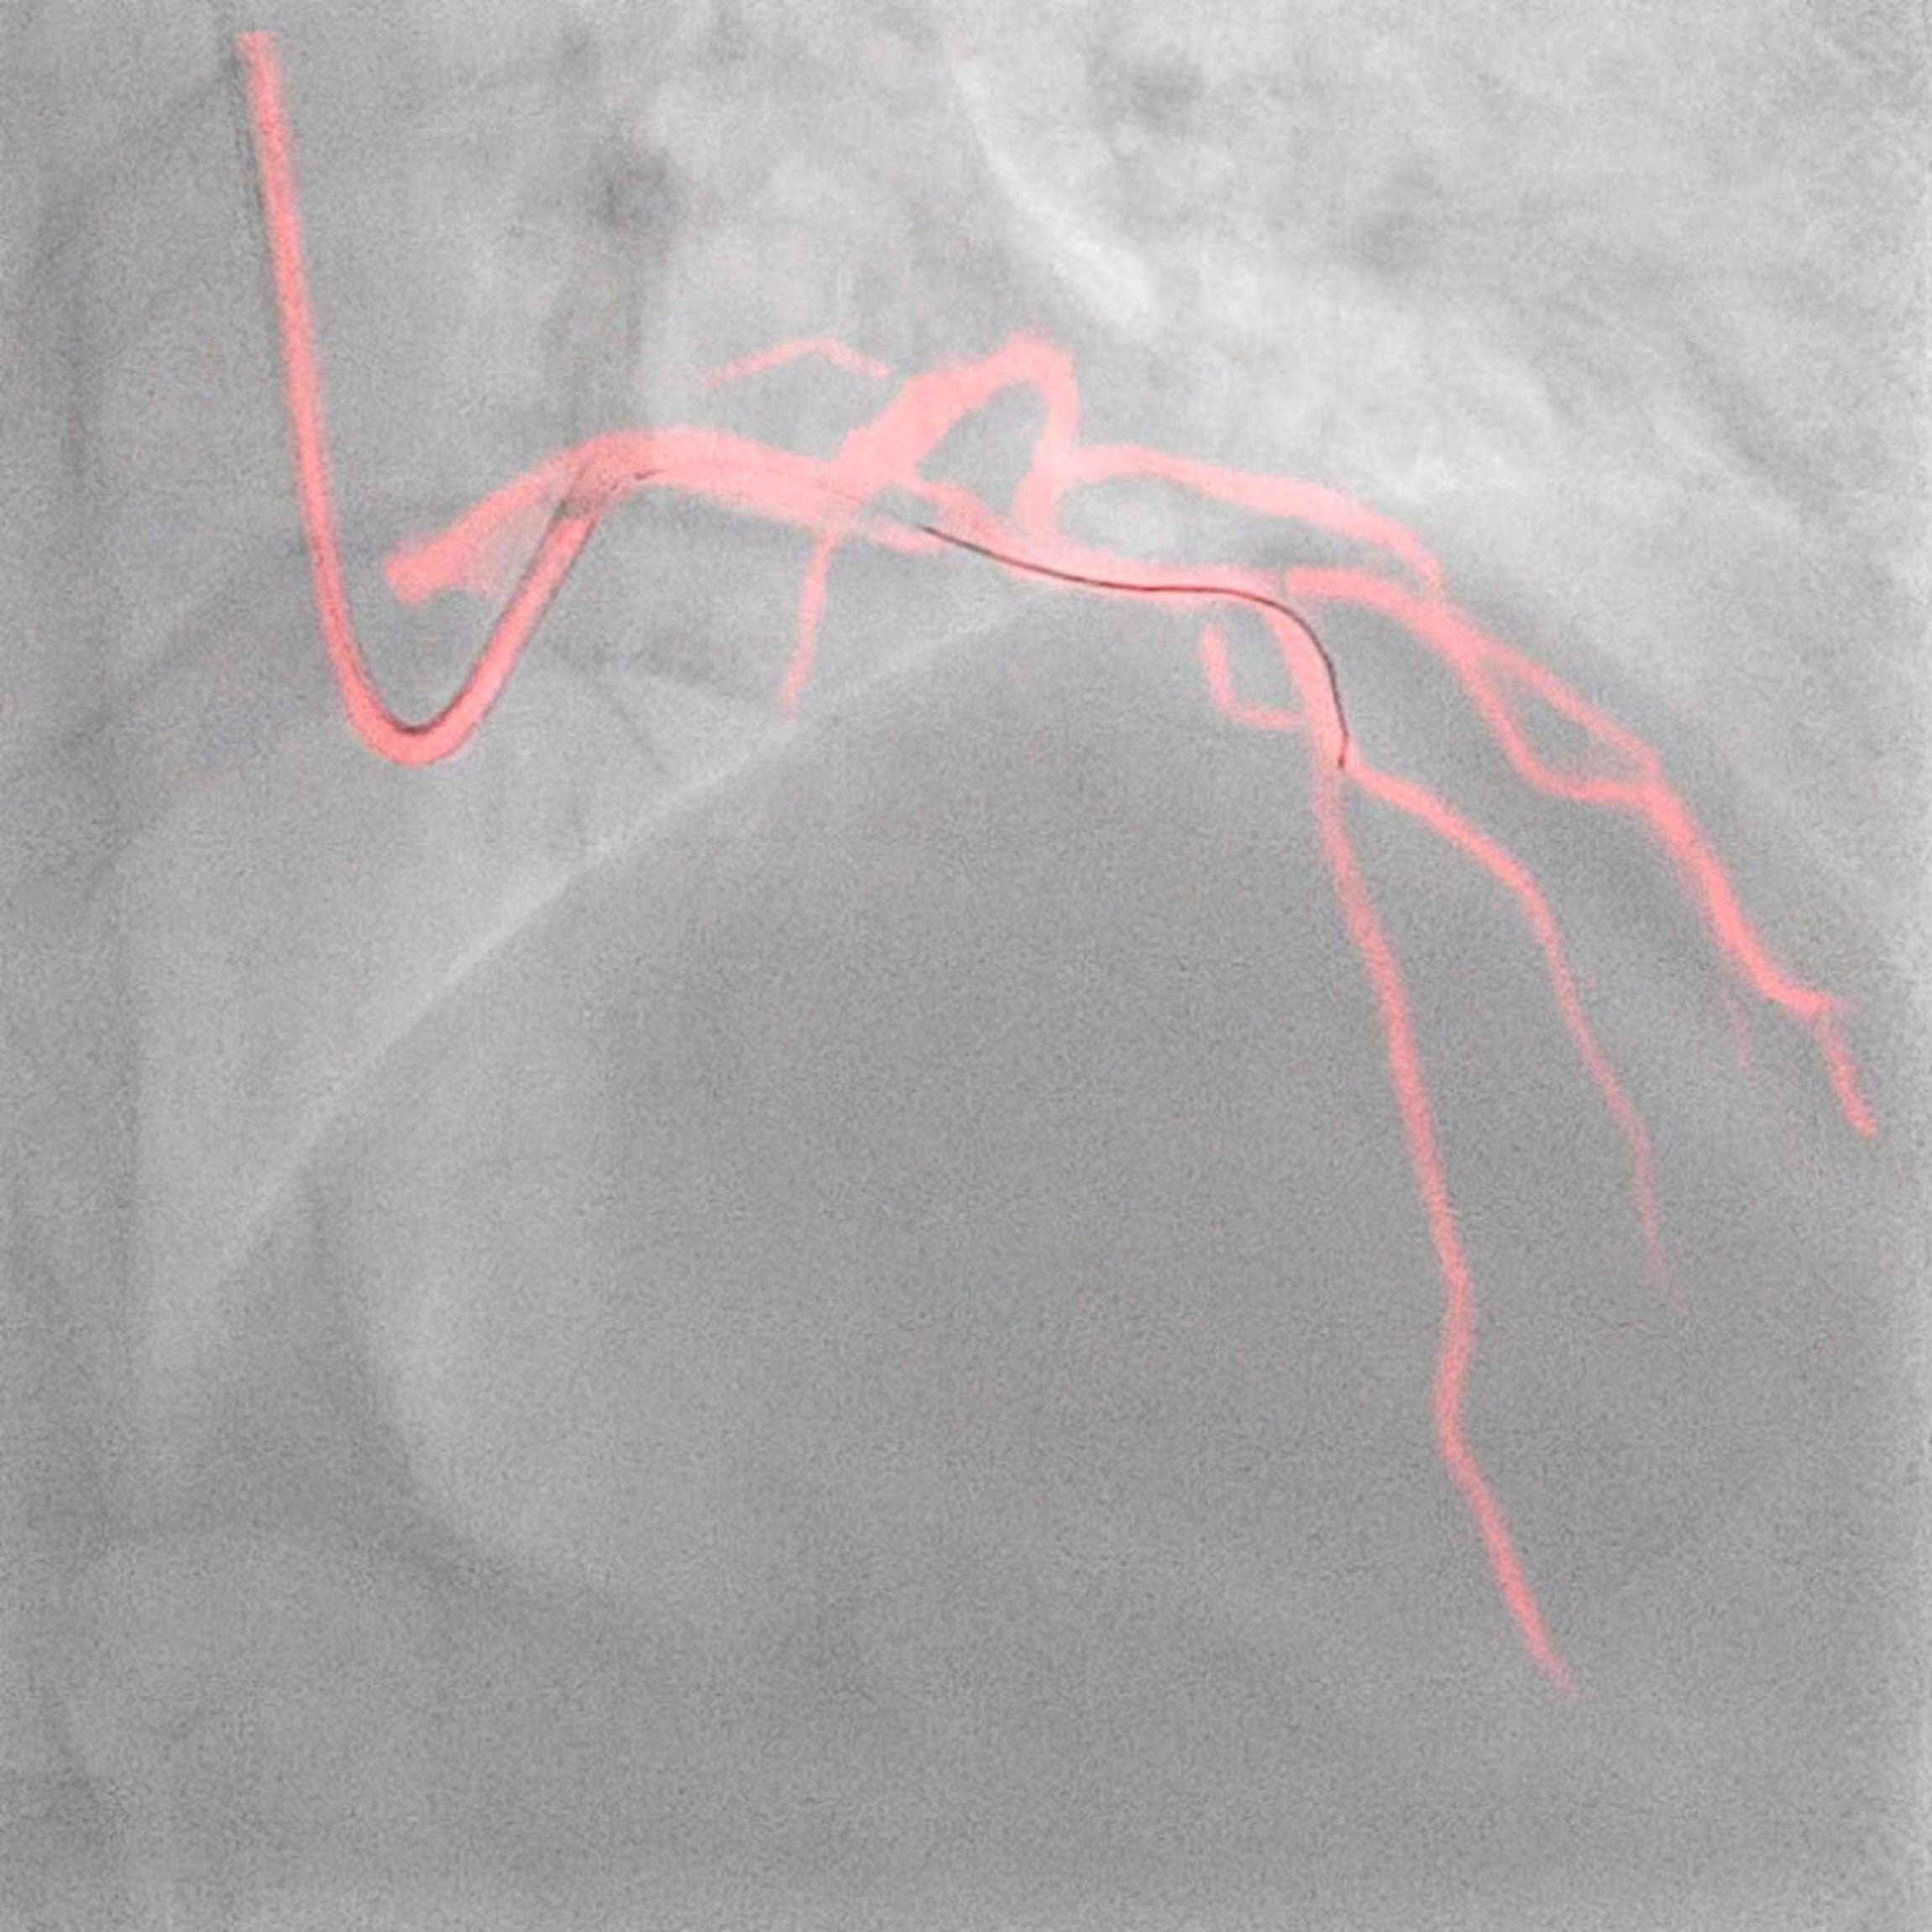

Amsterdam, the Netherlands – Royal Philips (NYSE: PHG, AEX: PHIA), a global leader in health technology, today announced late-breaking data from the DCR4Contrast (Dynamic Coronary Roadmap for Contrast Reduction) trial, the largest ever randomized controlled multicenter clinical trial to investigate the ability of Philips Dynamic Coronary Roadmap (DCR) to reduce the total iodinated contrast media volumes administered during percutaneous coronary intervention (PCI) procedures, compared to PCI performed without DCR guidance. The results were presented today at the European Association of Percutaneous Cardiovascular Interventions (EuroPCR) 2023 course and will also be presented later this week at the Society for Cardiovascular Angiography & Interventions (SCAI) 2023 scientific sessions.

The number of high-risk patients undergoing PCI procedures worldwide has increased significantly [2]. Iodine contrast media is used to visualize the coronary arteries during PCI procedures, but it can potentially harm the kidneys, risking the development of contrast-induced acute kidney injury (CI-AKI) after the procedure. The study found that Dynamic Coronary Roadmap reduced the total iodine contrast volume per procedure on average by 28.8% (95% Confidence Interval: 18.9%, 38.2%), and reduced the number of angiograms per procedure on average by three runs based on a procedure with an average of 11 runs or 26.3% reduction (95% Confidence Interval: 16.8%, 35.1%) [1].

Philips’ Dynamic Coronary Roadmap software is a real-time visualization innovation that removes the need for additional contrast media injections by overlaying the angiogram onto real-time motion-compensated 2D fluoroscopic imaging to provide interventionalists with continuous visual feedback on the positioning of guide wires and catheters. Complementing this technology, the Philips IntraSight precision guidance system streamlines lesion assessment, simplifies vessel sizing, enables precise therapy delivery and also supports the operator in their goal to reduce contrast volumes.